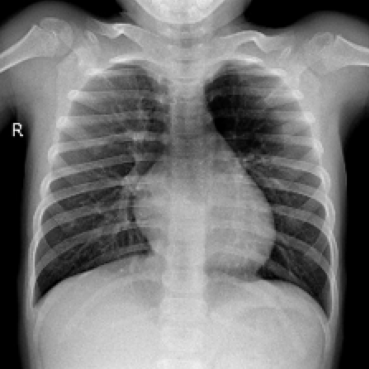

The impact of position guidance is visualized through the Class Activation Mapping (CAM) in Fig. 3. In the first row, the entire lung view fails to detect anomalies in the left region. However, specific views focused on the left, upper, and lower sections of the lung successfully identify these anomalies. In the second row, the left lung view detects anomalies that are missed in the entire lung view. These outcomes indicate the importance of utilizing diverse position prompts.